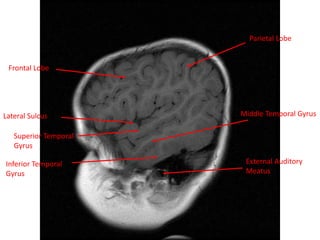

Frontal Lobe

Parietal Lobe

Superior Temporal

Gyrus

Lateral Sulcus

Inferior Temporal

Middle Temporal Gyrus

External Auditory

Meatus

. Bone

Frontal Lobe Parietal Lobe SuperiorTemporal Gyrus Lateral Sulcus Inferior Temporal Gyrus Middle Temporal Gyrus External Auditory Meatus